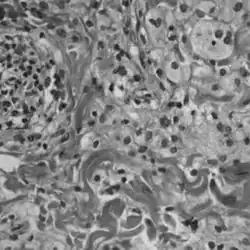

Histopathology slide of Erdheim-Chester disease | |

A definitive diagnosis of ECD is made when CD68-positive, CD1a-negative histiocytes are identified in a biopsy specimen.[2] ECD is marked by the buildup of foamy histiocytes and occasional Touton giant cells in a fibrous tissue background. Tissue samples show xanthomatous or xanthogranulomatous infiltration by lipid-laden histiocytes.[8] Lymphoplasmacytic infiltrates may be present but are usually sparse. The histiocytes in ECD typically show similar markers to reactive histiocytes, except when the BRAF V600E mutation is found. Classic signs, like foamy histiocytes, may not always be visible and could instead show general inflammation and fibrosis.[9]

Immunohistochemical staining (IHC) can assist in diagnosing and classifying ECD versus other histiocytic neoplasms such as LCH. Using BRAF V600E-specific antibodies in IHC testing provides high accuracy for diagnosing the former.[9] Unlike LCH, ECD does not stain positive for S-100 proteins or Group 1 CD1a glycoproteins, and electron microscopy of cell cytoplasm does not disclose Birbeck granules.[8] More sensitive methods like pyrosequencing or digital droplet polymerase chain reaction may be helpful if aforementioned methods return with inconclusive results.